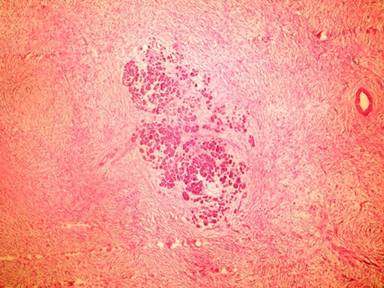

A tumor structure at 665 g weight and 18.5x11x6 cm size that has capsule at outer side has seen on macroscopic evaluation of radical resection specimen. It has seen that outer surface of tumor was smooth and sectional surface yellow and beige color in some areas (Figure 2). Microscopically, tumor infiltration of normal pancreas tissue consists from cells with eosinophilic cytoplasm, which were fusiform with hyperchromatic nucleus, having an undefined cytoplasmic border and encircled at outer part with a thin capsule (Figure 3). Extensive vascular walls were showing hyaline thickening. Hyalinization and myxoid degeneration areas were seen in parts, which were rich hypercellular (tumor rich) and hypocellular (collagen rich). One or two mitotic figure has been encountered in 10 high power fields. Widespread positive staining with vimentin and CD34 has been observed in immunohistochemical staining (Figure 4). It has seen that there was nuclear positive staining with beta-catenin (Figure 5) and focal cytoplasm staining with bcl-2. Negative results have been observed with S100, desmin and keratin. Ki-67 proliferation index has been observed below 2%.

Figure 3. Tumor infiltration of normal pancreas (20x H&E). |